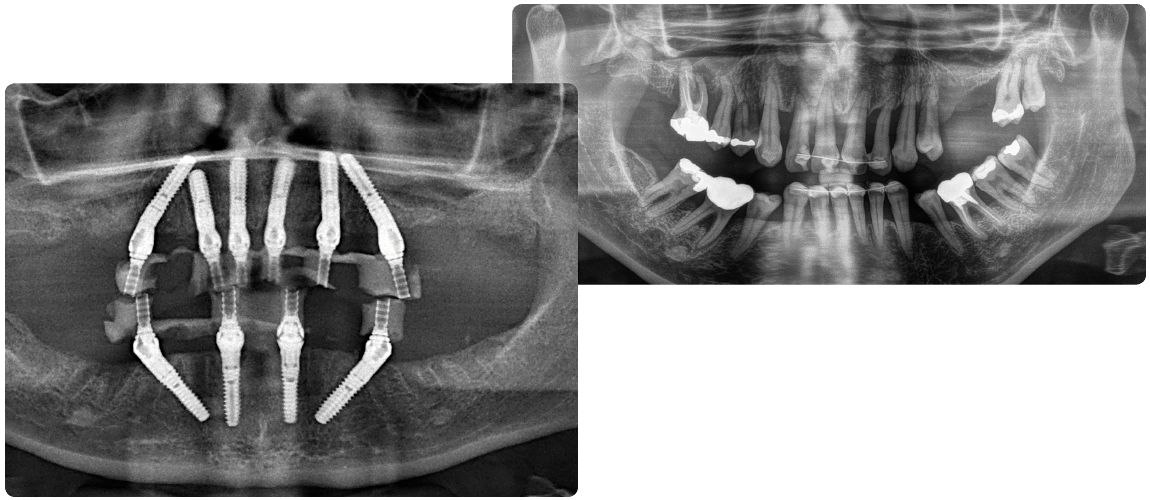

Fast & Fixed implant tekniği, tam dişsiz hastalarda belirlenen açılara göre yerleştirilen ; dört adet dental implant üzerine diş protezinin sabitlenmesini sağlayan bir yöntemdir.

Gerekli görüldüğünde implant sayısı 5 veya 6’ya çıkarılabilir.